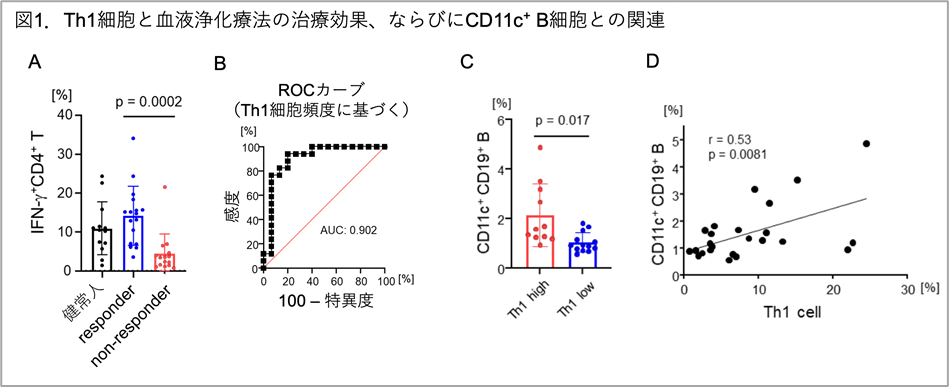

多発性硬化症に対する血液浄化療法の作用機序解明と個別化医療への期待

血液浄化療法を実施したMS難治例31例の解析により、同治療によって症状の改善がみられる例の特徴として、血液リンパ球の一種...